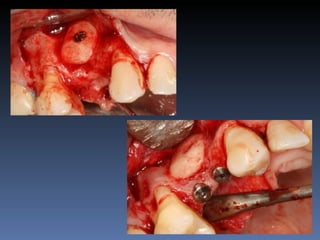

BOX 3

José Luiz Peretti

Idade – 67 anos

Sexo – Masculino

Raça – Caucasiana

ASA – II

Data- 23-04-2012

Diagnóstico: Desdentado parcial maxila

Plano de tratamento: Reabilitação da área desdentada

1.4,.1.5 com instalação de 2 implantes endo-ósseos

para reabilitação protética fixa .

O meu primeiro Implante